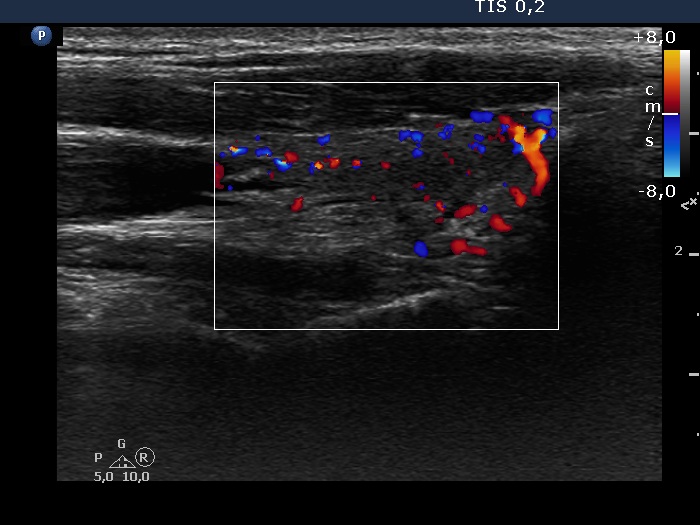

Second examination 14 months after the initial (4th row of images):

Ultrasonography: The size of the thyroid decreased dramatically and became atrophic. The right lobe still presented a small deeply hypoechogenic area. In contrast with the first examination, the basic echo structure of the left lobe was not normal but moderately hypoechogenic. The vascularization was decreased and average, right and left lobe, respectively.